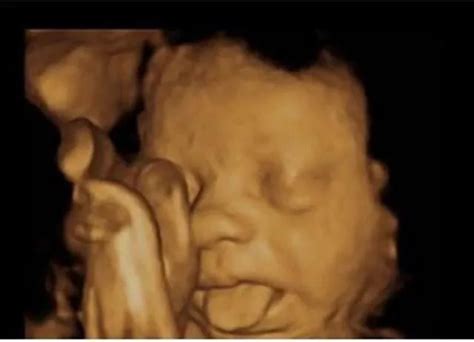

18周胎儿真实图图片(2)